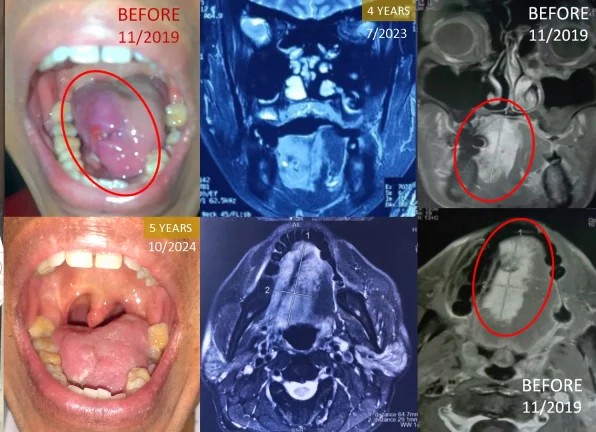

Saving the Voice: Surviving Stage 4 Tongue Cancer Without the Scalpel

5 Years of Cancer-Free Survival While Keeping the Tongue Intact

In 2019, Mr. Taufik Sarmin was diagnosed with Stage 4 Adenoid Cystic Carcinoma, a rare and painful form of tongue cancer. The tumor was massive, covering nearly the entire right side of his tongue. Faced with the medical recommendation of a glossectomy (surgical removal of the tongue)—which would permanently impair his ability to speak and eat—he chose ECCT as an alternative. The treatment process was grueling and painful as the cancer cells broke down into a thick liquid, but he persisted. Five years later, his tongue remains fully intact and functional. The dense tumor mass has been replaced by scar tissue, allowing him to live a healthy, active life with his speech and sense of taste preserved.